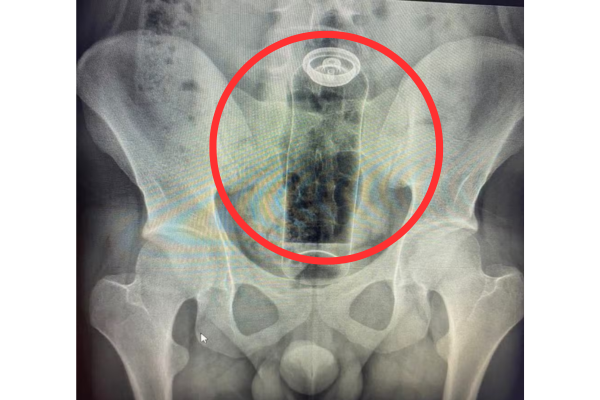

Um jovem de 19 anos precisou ser internado após ficar com um desodorante preso no reto durante uma prática sexual. O caso foi divulgado por um médico cirurgião coloproctologista como forma de alertar sobre os riscos da introdução de objetos inadequados na região anal.

De acordo com o médico Daniel Brosco, o paciente relatou que colocou o objeto durante uma “brincadeira” sexual, mas a embalagem acabou sendo sugada para o interior do reto, impossibilitando a retirada em casa.

Segundo o especialista, o intestino realiza movimentos naturais, conhecidos como peristaltismo, que podem puxar objetos introduzidos, fazendo com que fiquem presos rapidamente.